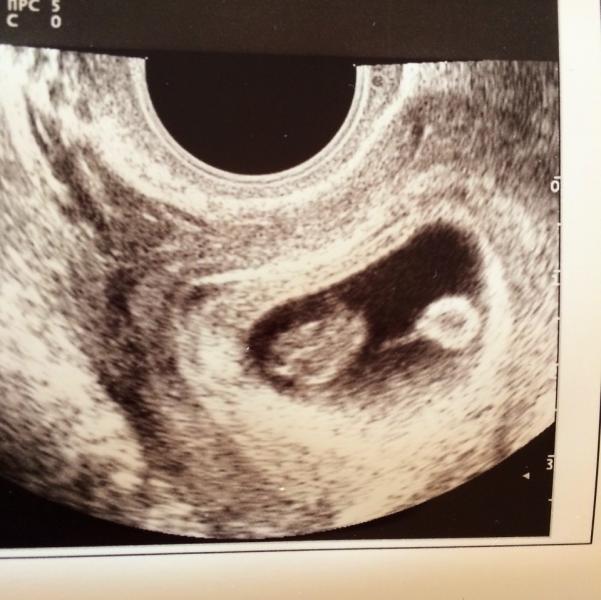

Все таки бывают положительные моменты нахождения в больнице. За неделю тут я уже привыкла к саркостическому лечащему врачу мандрыкина жанна анптольевна, подружилась с девочками по палате, а сегодня мне сделали заключительное узи. И врач узист просто золото. Все посмотрела, подтвердила, что матка у меня сзади, я спросила, что это за особенность такая. А это просто как у людей курносый нос, сказала, что когда рожать буду она выйдет вперед, а потом после родов снова назад. Она распечатала мне снимо...